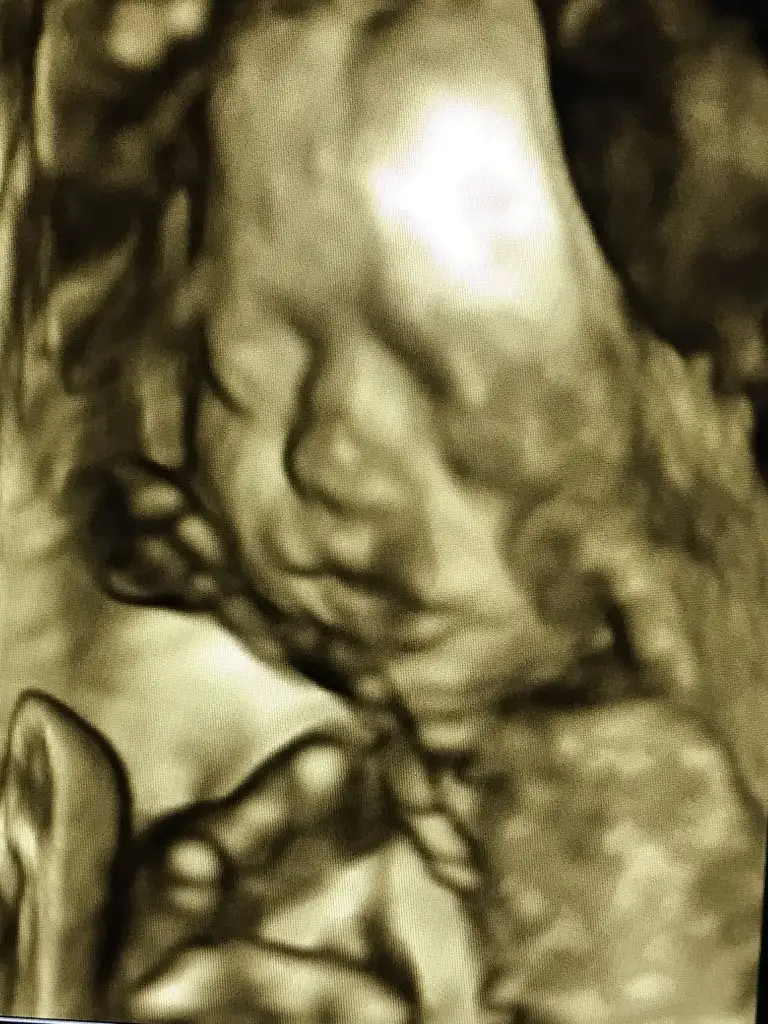

Yaaa o dudaklar nedir Allahımmm maşallah kızçeyeeŞansıma en kötüsü elmalı geldi limonlu beklerdimama içilmicek gibi değil kızlar içtim bitti bi anda. Şimdi kan vericem süreyi bekliyorum kızçem de beni üzmedi vee gösterdi yine yüzünü inanılmaz duygular inanılmazzzz

Ay maşallah yaaa ne kadar güzel çıkmışŞansıma en kötüsü elmalı geldi limonlu beklerdimama içilmicek gibi değil kızlar içtim bitti bi anda. Şimdi kan vericem süreyi bekliyorum kızçem de beni üzmedi vee gösterdi yine yüzünü inanılmaz duygular inanılmazzzz

Yaaa o dudaklar nedir Allahımmm maşallah kızçeyee

Dudaklar beni benden aldı zaten ahh minnak kızım ahhhAy maşallah yaaa ne kadar güzel çıkmışAllah kucağına aldığın günüde göstersin gelişimi nasıldı kilo boy